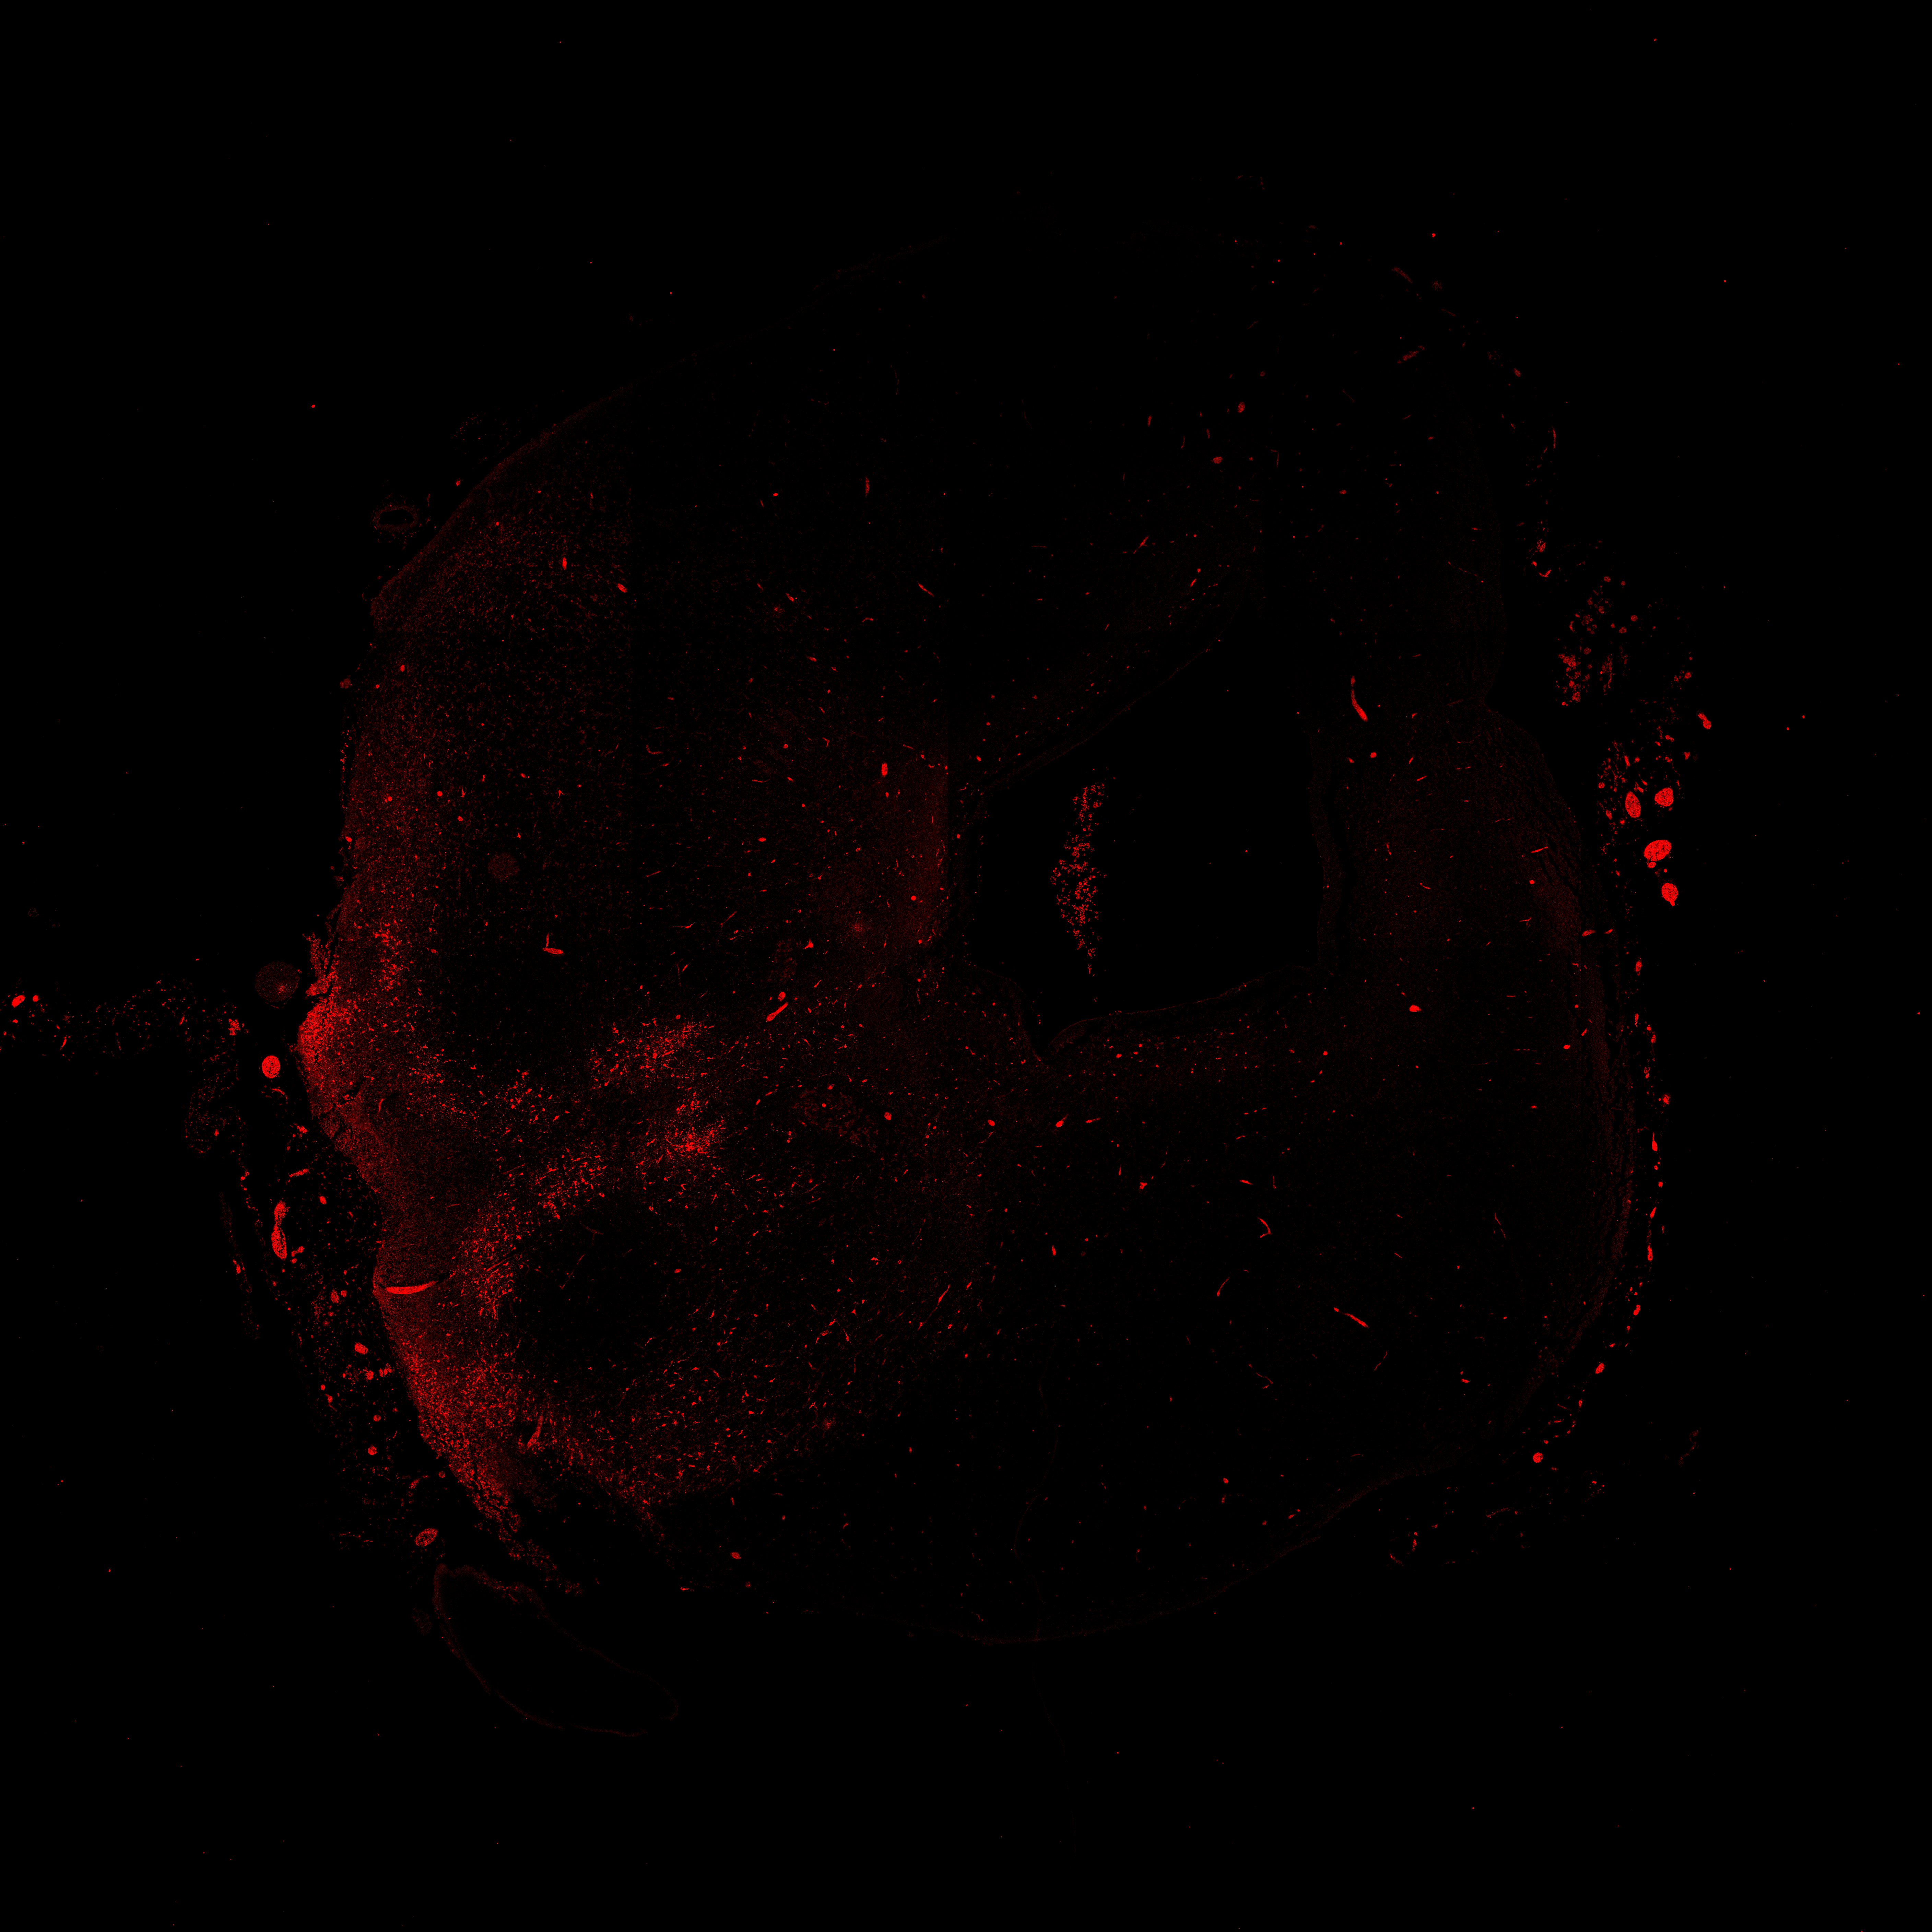

An anatomical analysis of the developing human midbrain from 6 post-conceptional weeks (PCW) to 22 PCW reveals increased tissue complexity, characterized by the emergence of dopaminergic nuclei, as highlighted by immunofluorescence analysis for tyrosine hydroxylase (TH).

17PCW

DAPI

17PCW human midbrain

MAP2

TH

Merged